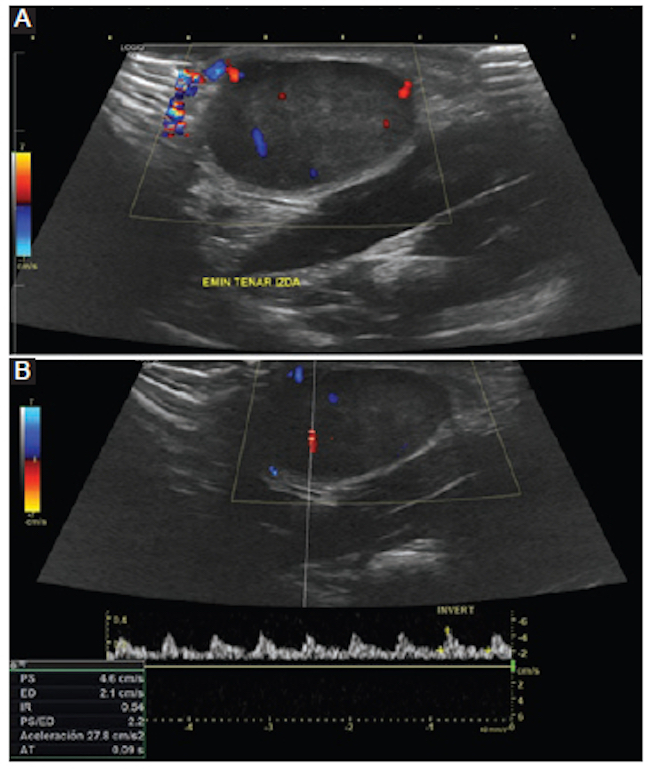

Se decidió realizar una ecografía de partes blandas de la palma de la mano, que demostró la existencia de una masa con apariencia tumoral sólida y sin características infiltrativas. Esta lesión era de morfología ovoidea, hipoecogénica, con unas dimensiones aproximadas de 30 × 15 mm (anteroposterior y craneocaudal), y contactaba en un punto con la epidermis. No se apreciaron cambios quísticos ni necróticos dentro de ella, si bien la señal de Doppler pulsado fue indicativa de vascularización arterial interna (Fig. 2).